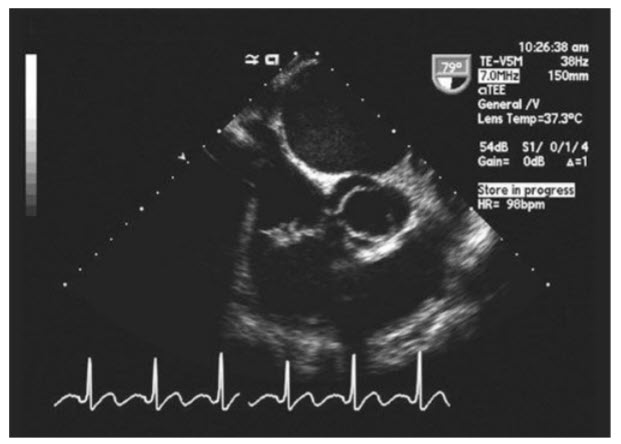

The following TEE image (Fig. below)

Bicuspid AV with fusion of the RCC and LCC. The 2D TEE midesophageal view (see Fig. in question) demonstrates a bicuspid AV in short axis. To determine cusp anatomy one must view the AV in systole. If one looks for a “Mercedes Benz” image of the valve in short axis during diastole (Fig. below A), one may mistake a bicuspid valve for a tricuspid valve, not realizing that one of the arms in the Mercedes Benz sign is actually a calcified raphe between two fixed cusps. Thus, it is important to look at the valve in systole to determine the true cusp anatomy. The most common form of bicuspid AV is fusion of the RCC and LCC. Bicuspid AVs are also associated with a dilated aorta with an aortopathy involving cystic medial necrosis. Another form of bicuspid AV is fusion of the RCC and NCC (Fig. below B). There are other congenitally abnormal AVs, including unicuspid valves (Fig. below C) and quadricuspid valves (Fig. below D). The unicuspid and quadricuspid valves are much less common than bicuspid valves.

A. Mid-esophageal short-axis view of the aortic valve (diastole). B. Midesophageal short-axis view of a bicuspid aortic valve with fusion of the RCC and NCC. C. Midesophageal short-axis view of a unicuspid aortic valve. D. Mid-esophageal short-axis view of a quadricuspid aortic valve.